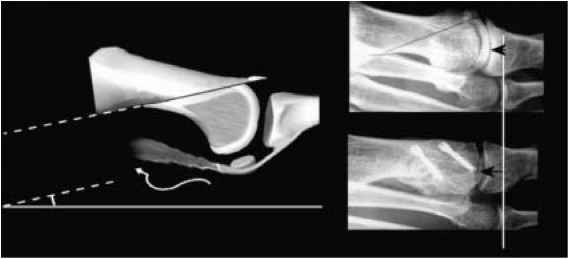

Decompressive metatarsal osteotomy

This involves shortening the metatarsal bone. The bone is cut at an angle and slid back or a small section of bone is removed. In either case fixation is used to maintain the new position whilst the bone heals. This procedure is selected when the 1st metatarsal is longer than the 2nd and when there appears to be adequate cartilage on the joint surfaces to allow movement.

Osteotomy of the proximal phalanx (big toe)

A wedge of bone is removed from the proximal phalanx (bone at the base of the big toe) and gap closed and held with a screw or wire. The procedure elevates the big toe allowing the individual to rock of the toe, this can help reduce pain when walking.